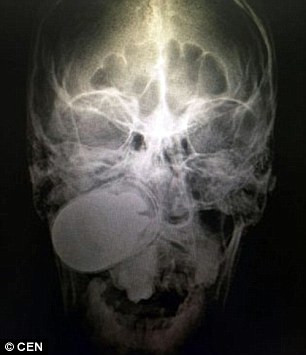

Hình chụp Z-quang mặt bệnh nhân